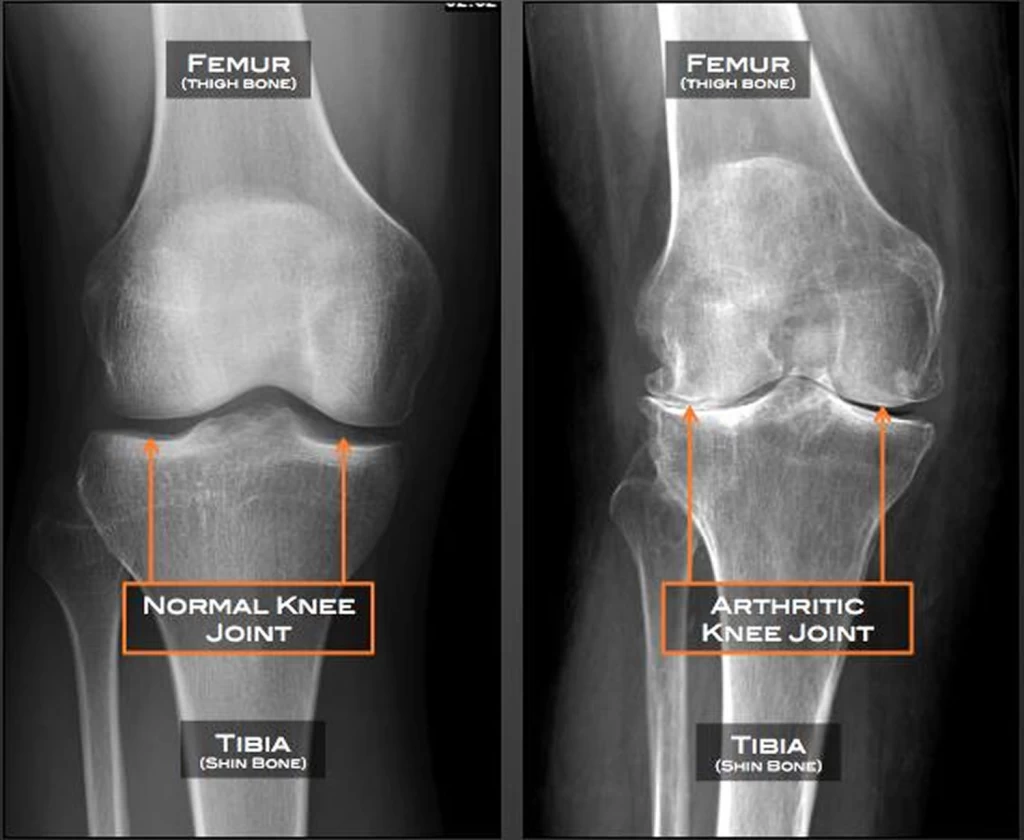

آرتروز زانو یکی از شایع‌ترین بیماری‌های مفصلی است که معمولاً با درد، تورم و کاهش حرکت مفصل زانو همراه است. این بیماری به دلیل تخریب تدریجی غضروف مفصل ایجاد می‌شود و می‌تواند تأثیر چشمگیری بر کیفیت زندگی افراد داشته باشد. در این مقاله به بررسی راهکارهای پیشگیری، روش‌های درمان غیرجراحی و جراحی‌های نوین برای آرتروز زانو می‌پردازیم. همچنین نقش متخصصان ارتوپدی مانند دکتر علیرضا صحرانورد در این حوزه بررسی خواهد شد.